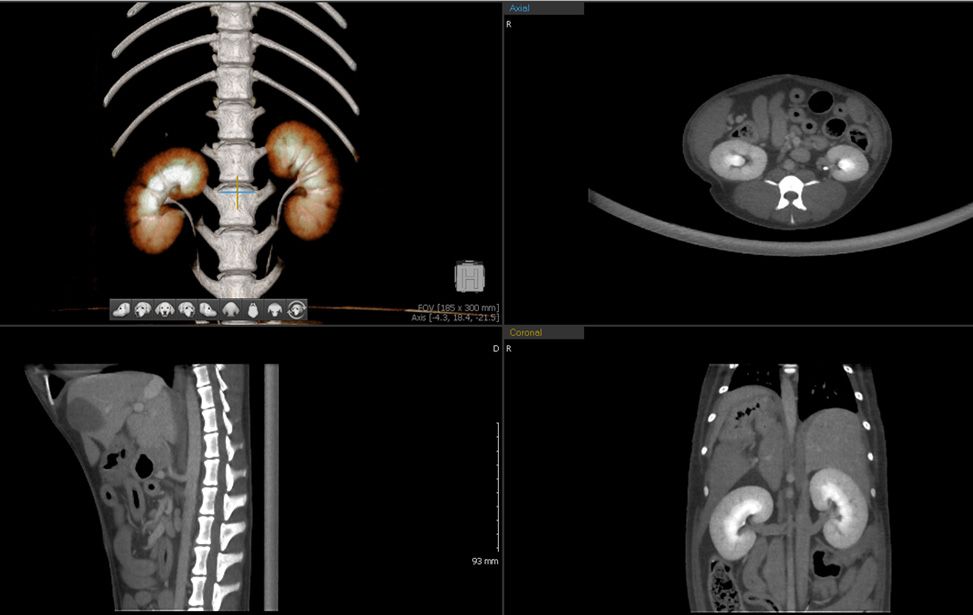

The innovative MyVet CT i3D with spiral linear detector technology brings multi slice CT image quality at a very affordable total cost of ownership right to your practice. Unique sensor design and proprietary image processing development provide you with high image quality especially in soft tissue thoracic and abdominal studies.

Simplified operation and imaging protocols optimizes staff workflow, productivity, and diagnostic results. Fast scan times, MPR and standard 3D volume rendering functionality facilitates obtaining diagnostic results as well as minimizing animal time under anesthesia.

- Superior soft tissue image

Reduce Scatter Radiation, Obtain High Image Quality

Unique detector design reduces scatter radiation resulting in better soft tissue visualization. A 0.4 / 0.8 mm acquired and 0.1 – 30 mm recon slice thicknesses maximize diagnostic information.